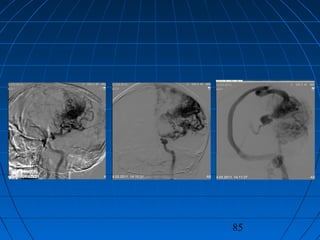

 İ.A.: 27 yaşında erkek hastaİ.A.: 27 yaşında erkek hasta

 BaşağrısıBaşağrısı

CERRAHİCERRAHİ

 Sol oksipital kranyotomiSol oksipital kranyotomi

 AVM’nin total rezeksiyonuAVM’nin total rezeksiyonu

 PostoperatifPostoperatif

Nörolojik Muayene ve DSA:Nörolojik Muayene ve DSA:

NormalNormal